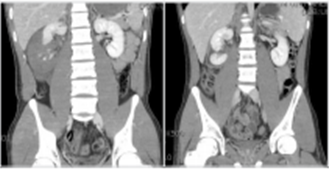

그림의 환자는 우측 lower pole의 shattered injury를 받았으나 생체활력징후가 양호하고 연령이 어려서 집중관찰한 경우이다. 우측 사진은 동일 환자에서 1개월 후 CT사진이다(Grade V).